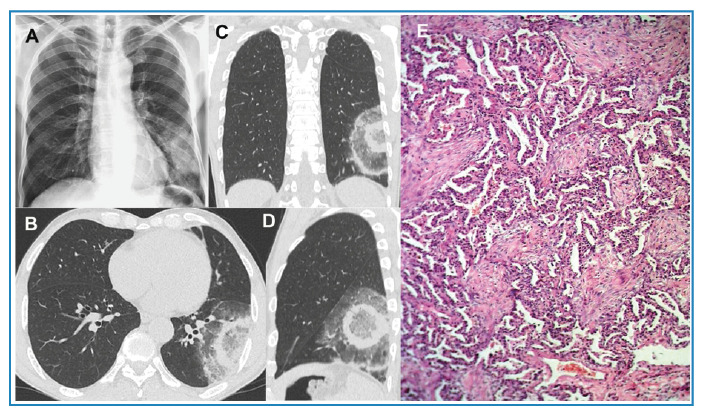

The CT target sign as a criterion for the differential diagnosis between tuberculosis and organizing pneumonia.

CT靶征作为结核与组织性肺炎鉴别诊断的标准。